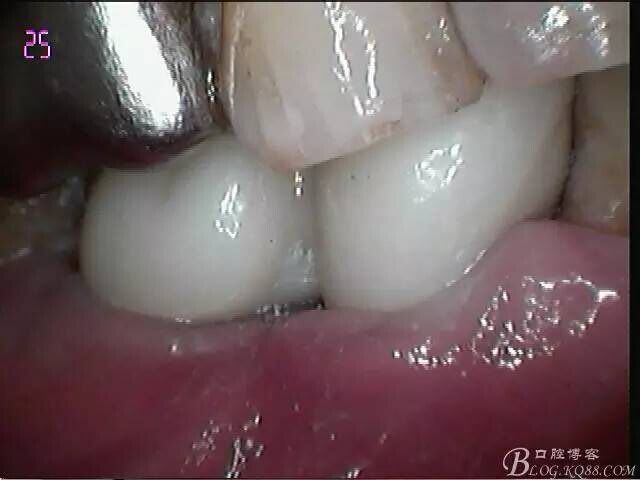

一月復(fù)查,上皮袖口封閉良好,牙齦恢復(fù)正常外形凸度,但近中齦乳頭仍不理想

試戴個(gè)性化基臺(tái),牙齦外形穩(wěn)定

口外粘接后,口內(nèi)螺絲固位

檢查邊緣封閉及靜態(tài)密合

牙齦封閉良好,咬合,近中觸點(diǎn)穩(wěn)定

樹脂封閉螺絲孔